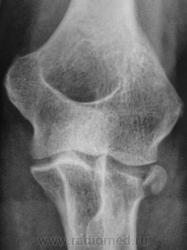

Травма. Пациент направлен на рентгенографию локтевого сустава.

Краевой  перелом  головки  луча.

Интересно, а как правильнее написать - перелом или откол фрагмента костной ткани?

Перелом оскольчатый, есть поперечная линия перелома головки луча на боковом снимке, + осколок наружного края. И очень похоже на выпот (гемартроз).

Я бы написала - краевой внутрисуставной перелом головки лучевой кости с угловым смещением

Правильно писать-краевой отлом наружного угла головки лучевой кости.